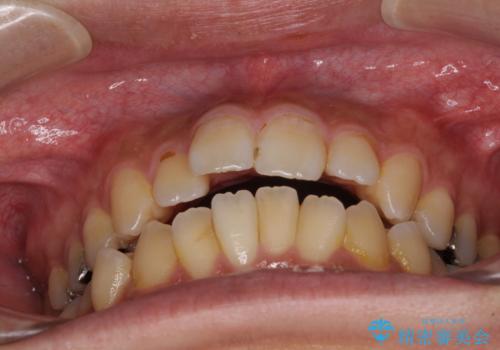

オープンバイトと目立つ銀歯 インビザライン矯正とセラミック修復治療

- 奥歯の目立つ銀歯と上下前歯の叢生と隙間を気にして来院された患者様です。

開咬の治療は、前歯を閉じるように動かすとともに、上下臼歯を圧下(骨内にめり込ませる)させることで進めて行きます。

インビザラインは臼歯の圧下を効果的に行えるため、インビザラインを用いて矯正治療を行うこととしました。